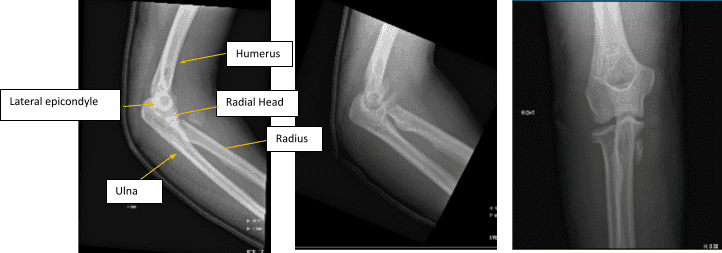

Figure 1. AP Oblique and Flexion Lateral Projection of Right Elbow

Hemarthrosis and a comminuted, affected, acute radial head fracture is present. The plantar-medial portion of the proximal shaft of the right ulna is home to a fracture fragment that has been severely misaligned. Though no donor defect is visible, this could be a fragment of the radial head that has been significantly displaced. A second fracture site is also a possibility.